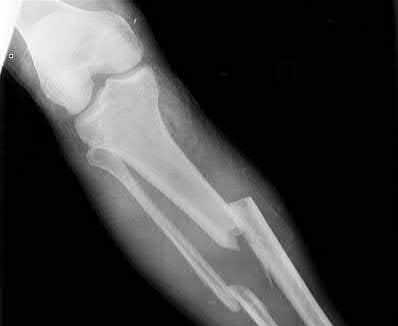

A 55-year-old female presents to the emergency room after falling off her balcony. She sustained the isolated, closed injury shown in Figures A and B. She is otherwise healthy, but routinely smokes 30 cigarettes per day. What would be the most appropriate sequence of treatment steps for definitive management of this injury?

5) Closed reduction and splinting, external fixation, CT scan, delayed open reduction internal fixation

Figures A and B show radiographs of a comminuted AO/OTA C3 fracture of the distal tibia. The most appropriate steps in the management of this patients injury would include: Closed reduction and splinting, external fixation, CT scan, and delayed open reduction internal fixation in this sequence.

Infection and wound healing problems are common with comminuted distal tibia fractures due to an increased incidence of soft-tissue complications associated with the operative management. Patients with a history of diabetes and smoking are at further risk. To decrease the risk of complications in this patient, a two-staged, delayed open reduction internal fixation technique is the best option for the treatment of severe pilon fractures.

Patterson et al. reviewed 23 consecutive patients with comminuted distal tibia fractures. They showed 0% infections or wound-healing problems in their patient population treated with a two-staged protocol. Their protocol involved fibula fixation with an intramedullary implant and application of a medial external fixator to to regain length and restore anatomic alignment. Re-evaluation of the limb occurred ten to fourteen days later for definitive fixation.

Sirkin et al. retrospectively reviewed 40 closed and 82 open pilon fractures (AO types 43A-C) that were treated with staged surgical management (avg. time from ext. fix. to formal reconstruction was 14 days (range 4 to 31) They reported 17% post-operative wound complication in the closed group and 11% post-operative wound complication in the open group (Gustilo Type I-III). They suggest the technique was successful in both closed and open pilon fractures.

Illustration A shows open reduction internal fixation of the above injury. Incorrect Answers:

Answer 4: CT scan is most appropriate after frame application. This will allow for distraction and indirect reduction of the fragments to better characterize the fracture pattern for pre-operative planning.